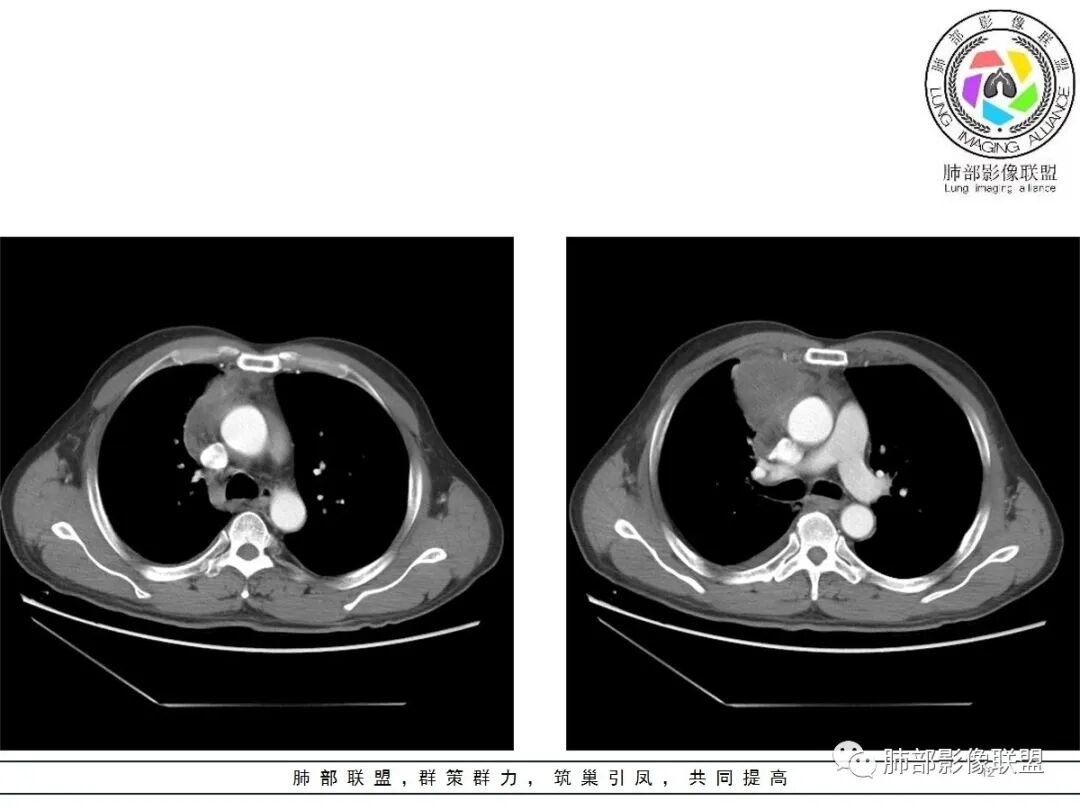

一切∮随缘:定位肺外,病变位于右前纵隔,与肺部交接面清晰,有胸膜尾征,心包局部受压,部分包绕主动脉血管,平扫密度均匀,形态规则,膨胀性生长,增强扫描壁有强化,内容物无明显强化,考虑1:淋巴瘤2:胸腺瘤3:神经鞘瘤4:支气管囊肿

廖鹏飞:可疑胸腺动脉进入肿块

廖鹏飞:考虑胸腺瘤合并感染,畸胎瘤待排

周围脂肪间隙密度增高,内部小点状很低密度影

右侧少量胸水

脂肪密度明显,还有钙化、囊性病变,支持含脂质类病变破裂

肿瘤样病变破裂所致纵隔炎应该没错

南边:肿瘤或肿瘤样病变破裂所致纵隔炎,这是大方向

结果:符合B型胸腺瘤伴出血,坏死囊性变,局部脓肿形成

3.右上纵隔囊实性占位,边界清楚。中央见点状脂肪密度影,边缘见一点状钙化影,增强不均匀环形强化。